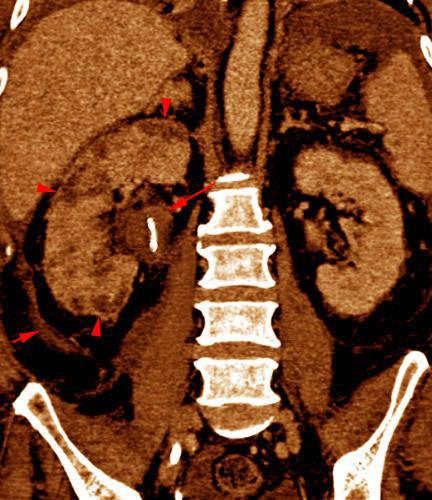

Abscesos renales en pionefrosis